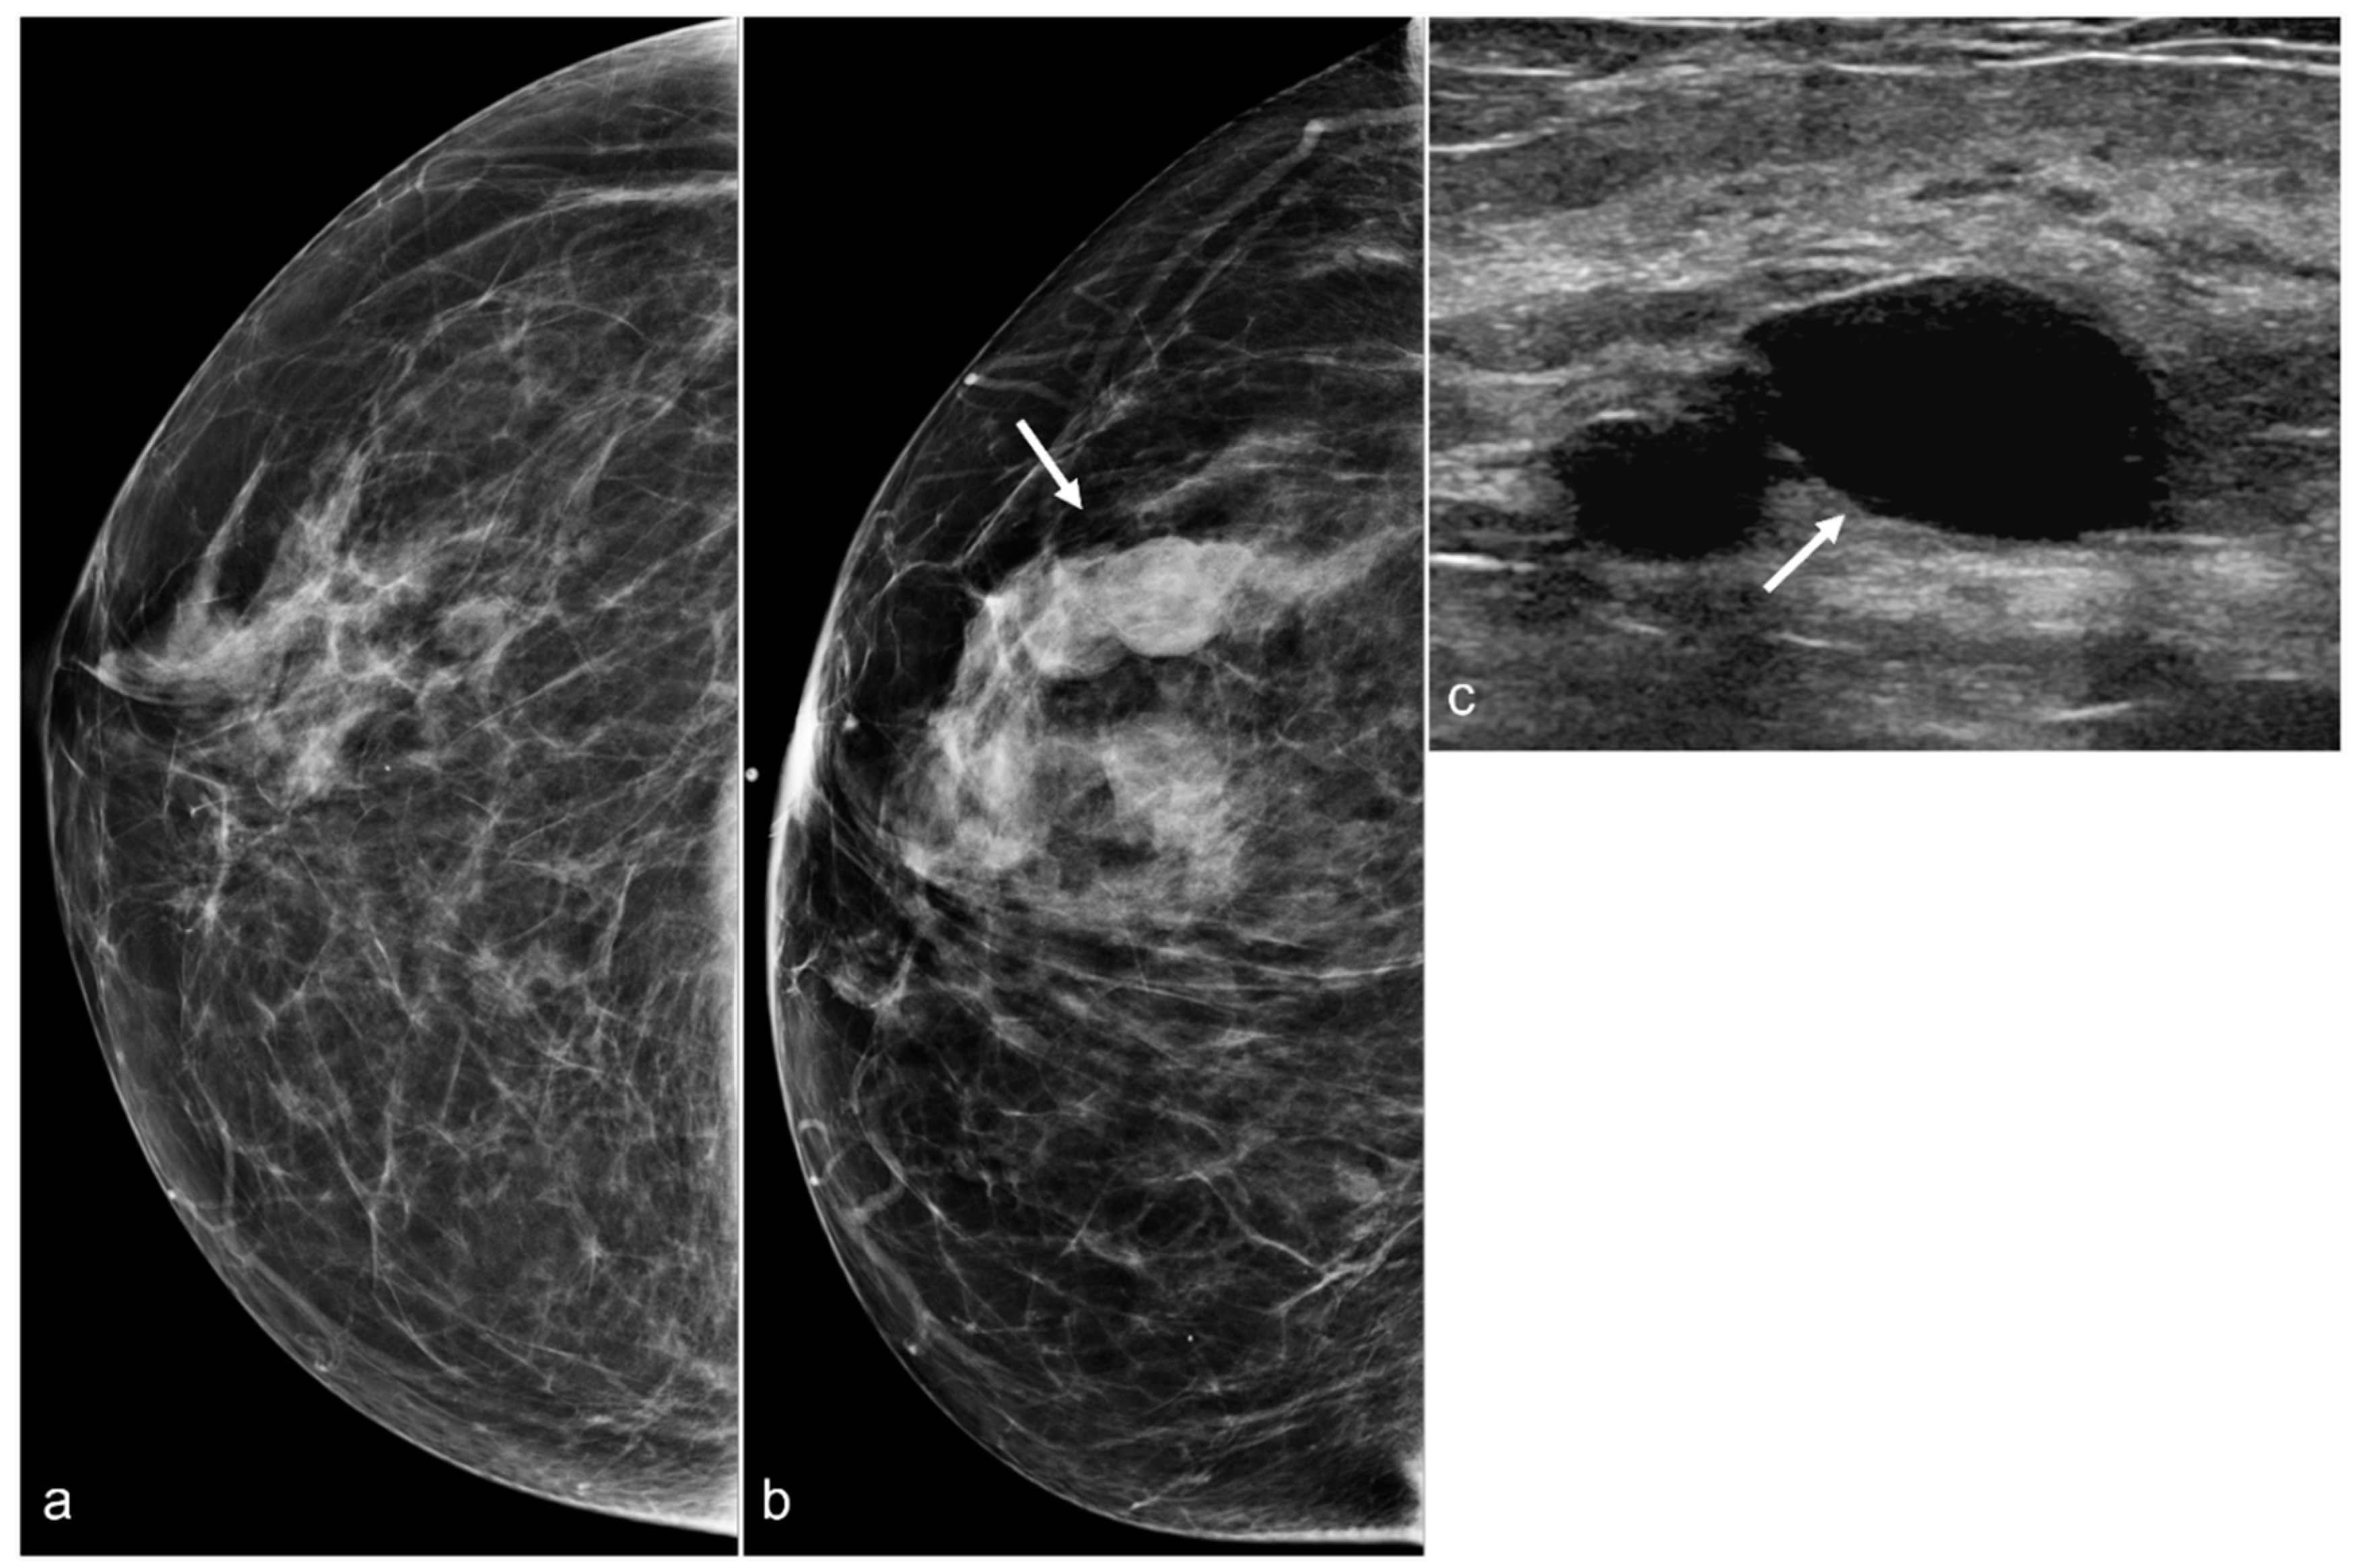

Figure 17. A 50-year-old woman with a history of subglandular silicone implants, status post BES. Screening mammograms with bilateral CC (a) and MLO views (b) demonstrate a mass in the left breast upper outer quadrant (arrowhead). BES changes are more prominent in the right breast with focal asymmetries in the prepectoral region (arrows) with dystrophic calcifications. Subsequent ultrasound examination of the left breast in the transverse plane (c) with ultrasound-guided biopsy revealed triple-negative invasive ductal carcinoma. T1-weighted post-contrast MRI (d) revealed a left breast enhancing mass (arrowhead) with a biopsy clip. There was also right greater than left prepectoral fluid (arrows) on the axial T2-weighted images (e).